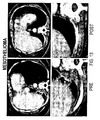

- Figure 13 is a CT scan of a mesothelioma tumor from a patient, before (PRE - left panel) and after (POST - right panel) treatment with SAHA twice daily at a dose of 300 mg three days a week for 6 months.

- the data demonstrates that SAHA is effective at treating mesothelioma tumors in patients.